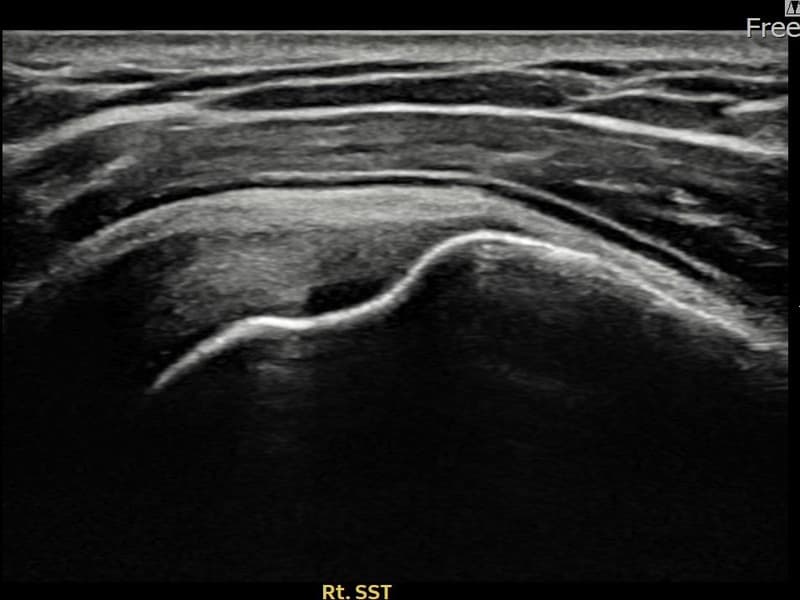

施術後

術前超音波にて右 棘上筋腱 付着部部分断裂・右肩棘上筋腱のエコー不連続と腱欠損(10mm × 4mm (腱厚の約42%欠損))を確認。術後超音波では断裂部位が再生組織で充填され、腱の連続性回復とエコーパターンの正常化が確認されました。